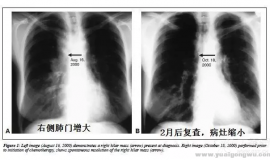

图片是详细治疗记录,以下是简单概述:患者女,55岁,肺腺癌,L858M和L861Q组合罕见突变,2020年9月确诊,2022年10月肺部做了放疗,阿法替尼吃到2023年6月,发现脑膜转移,吃了一两个月的标准剂量的伏美替尼,在这期 ...